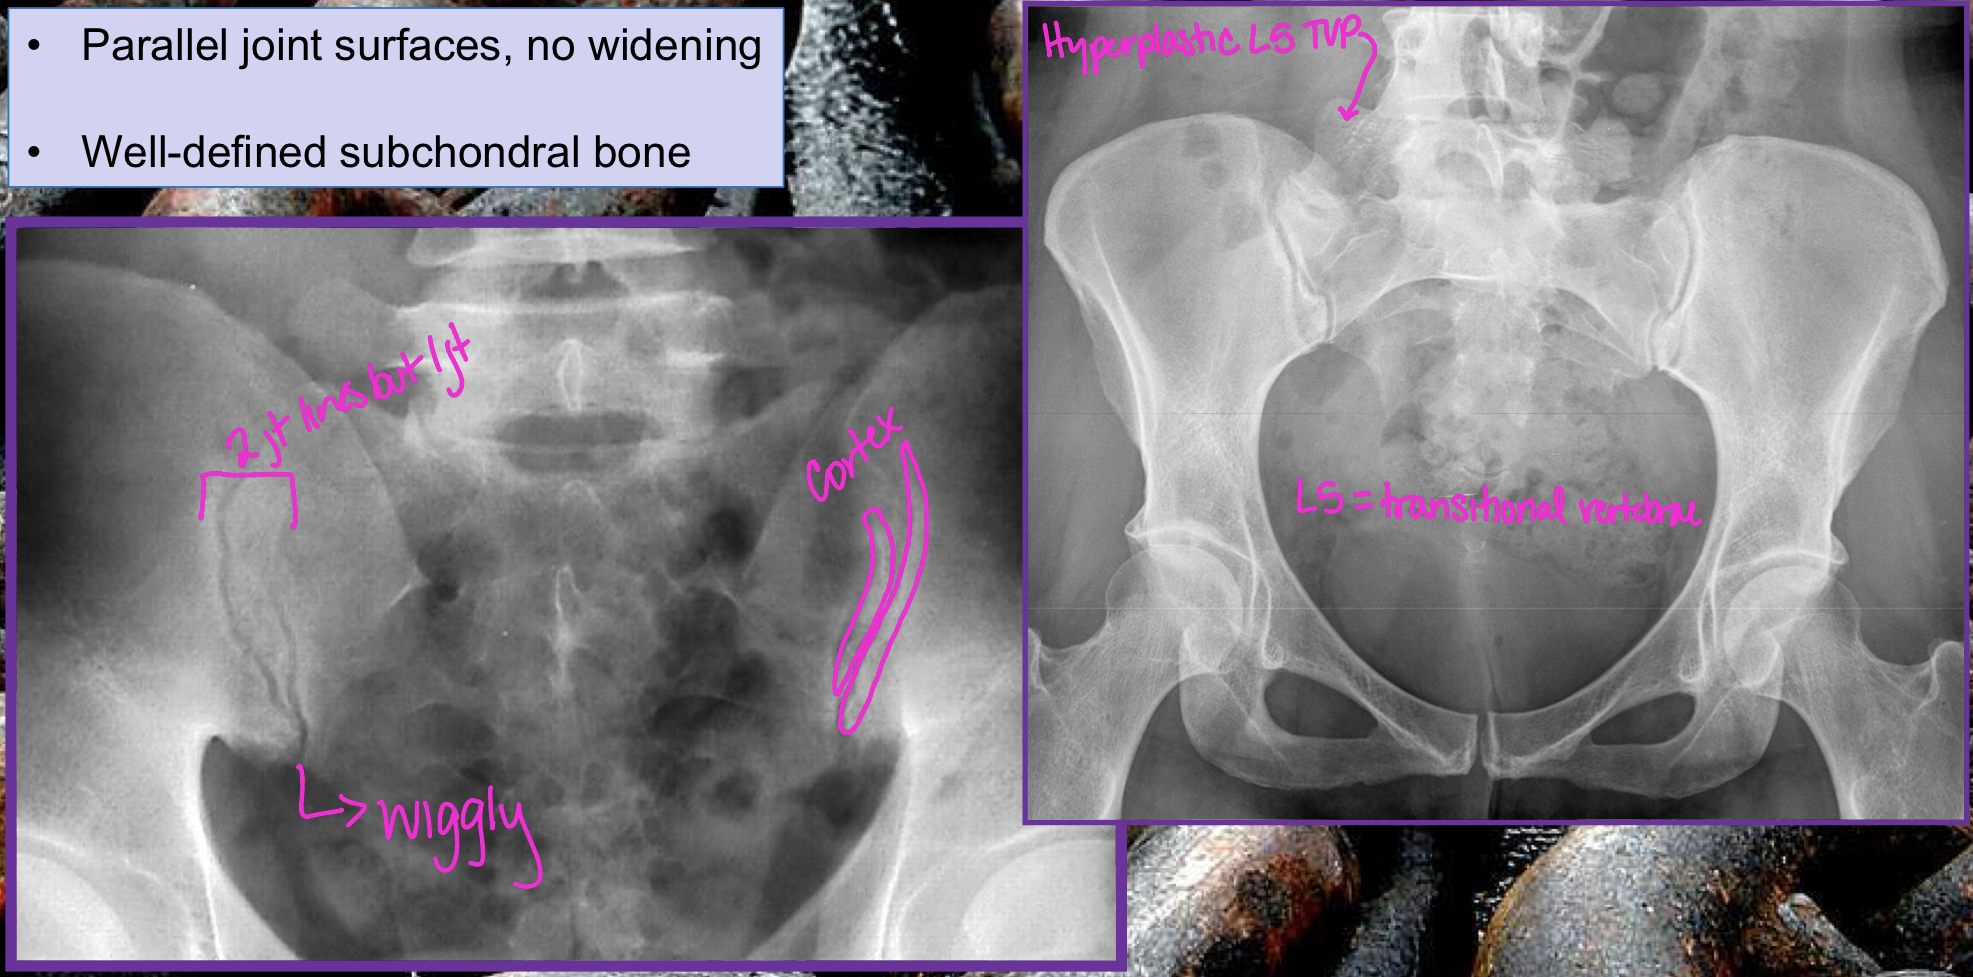

Normal SI joints

AS Sacroilitis grading

0 - normal SI joint width + sharp joint margins

1 - suspicious

2 - sclerosis, some erosions

3 - severe erosions, pseudo-dilation of joint space, partial ankylosis

4 - complete ankylosis

Why is this image’s dx NOT Osteitis Condensans Ilii (OCI)

b/c erosions

What are the two dx of these images (left vs right)

Left = PsA

Right = AS